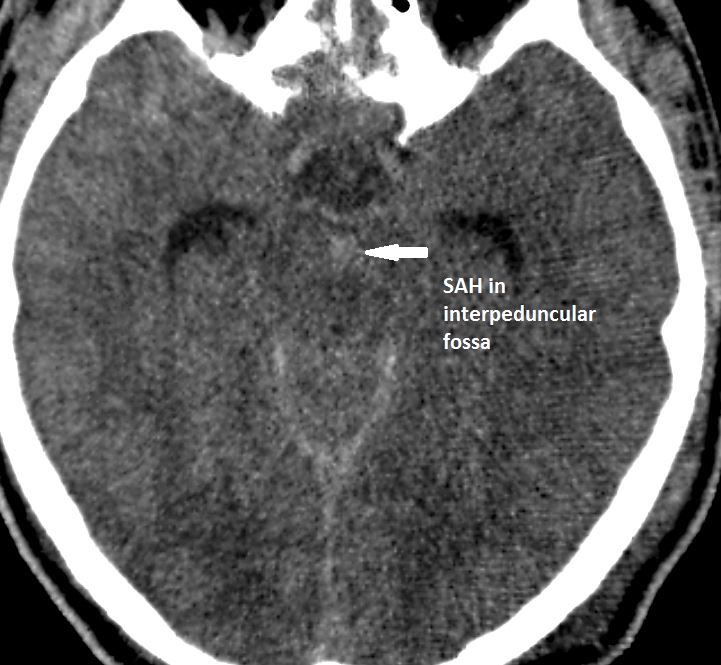

Central Skull Base and Calvarium

There is injury of the fronto-nasal- ethmoid complex. Specifically, the ethmoid roof, olfactory fossa and the cribriform plate are fractured and/or significantly dehiscent.

The frontal bone and frontal sinus inner and outer tables are fractured.

There is fracture of the greater or lesser wing of the sphenoid bone, optic strut and canal, or basisphenoid, in the region of the orbital apex.